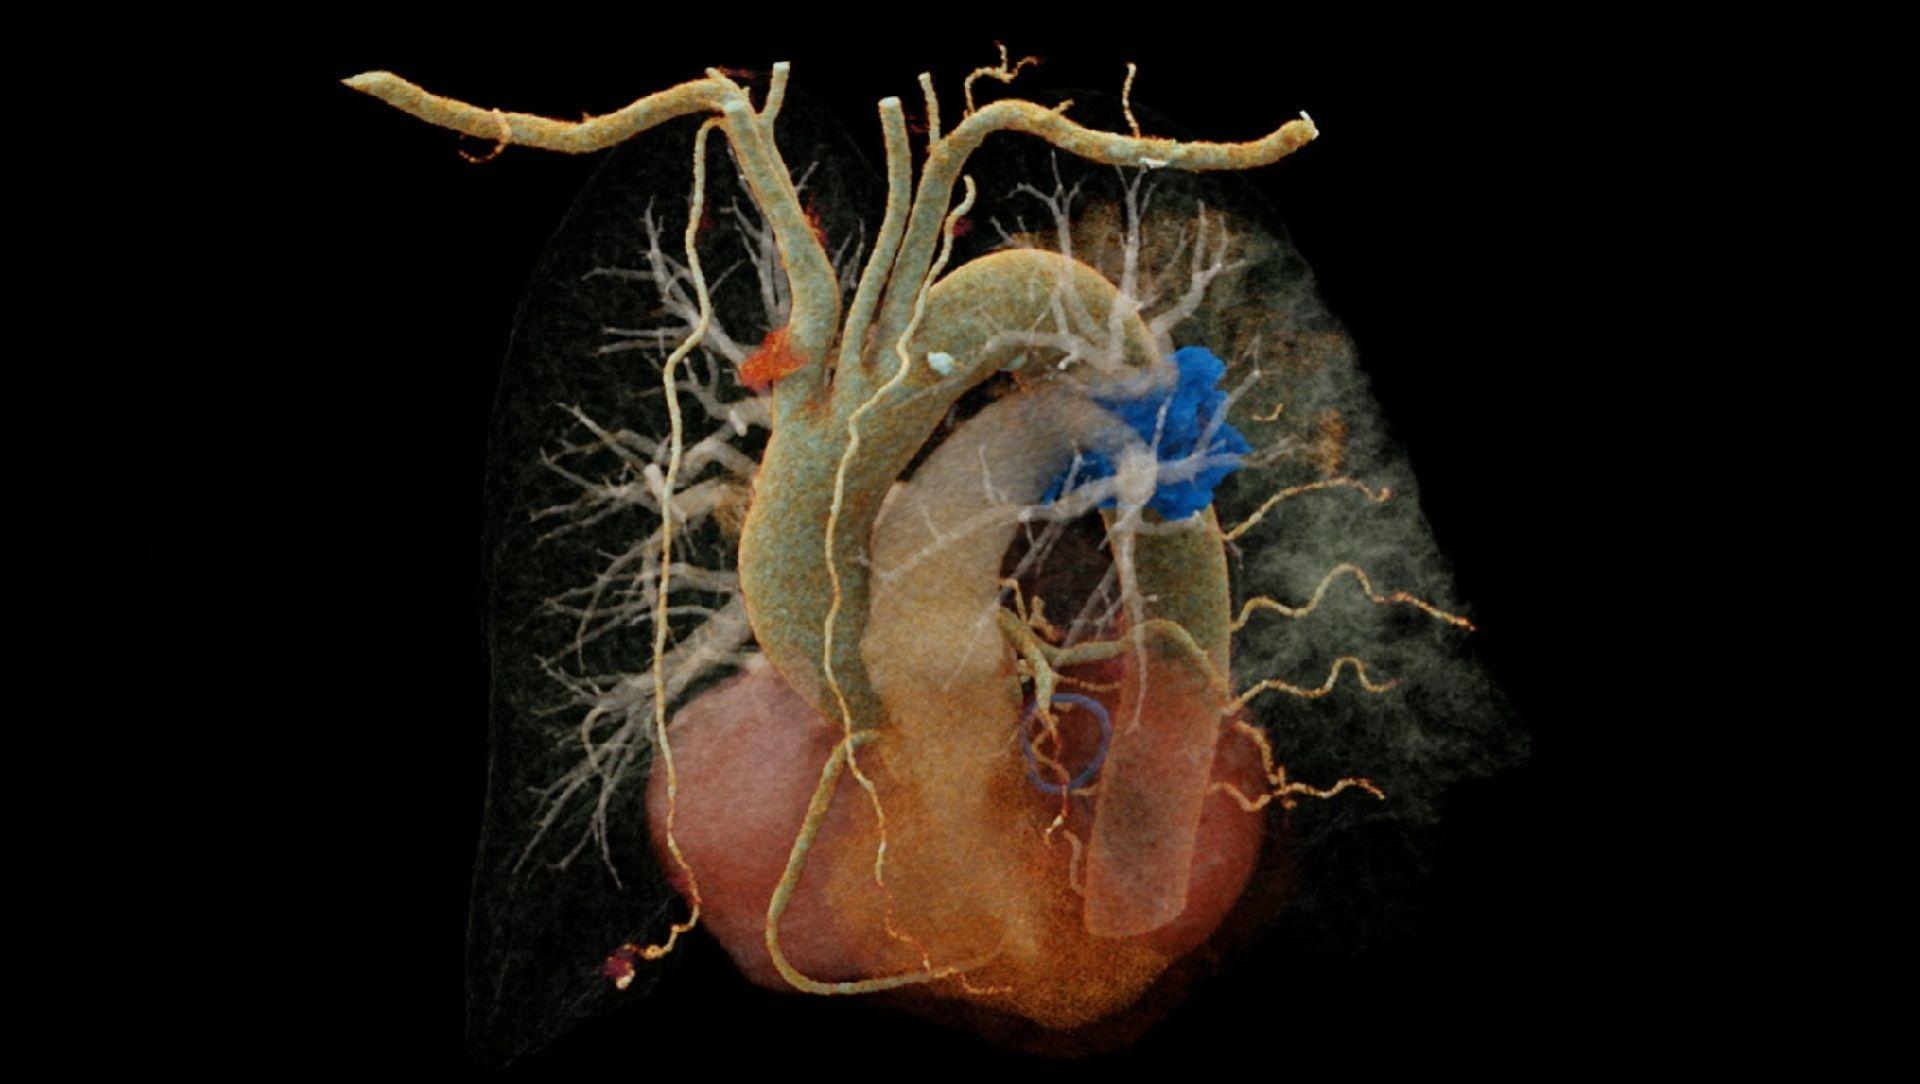

NAEOTOM Alpha and its Quantum Technology are revolutionizing CT use in the field. Stay up to date on all the latest discoveries and highlights from colleagues around the world as they exploit the advantages and potential of its ultra-high resolution, inherent spectral imaging, and clinical insights supporting your diagnostic precision available across a variety of clinical fields. We’re collecting all the highlights as they come in, gathered here in one spot for your convenience. Check in again soon!